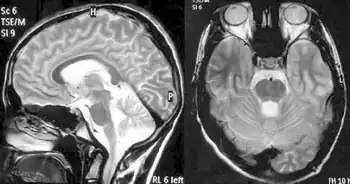

Balance difficulty, loss of proprioception, an absence of reflexes, and signs of other neurological problems are common signs from a physical examination.[10][25] Diagnostic tests are made to confirm a physical examination such as electromyogram, nerve conduction studies, electrocardiogram, echocardiogram, blood tests for elevated glucose levels and vitamin E levels, and scans such as X-ray radiograph for scoliosis.[26] MRI and CT scans of brain and spinal cord are done to rule out other neurological conditions.[27] Finally, a genetic test is conducted to confirm.[27]